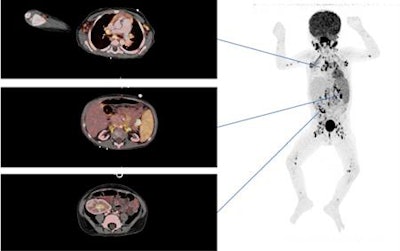

The researchers retrospectively and consecutively looked at both children and adults who received a transplanted heart, lung, liver, or kidney at Rigshospitalet between January 2004 and May 2015. All patients underwent a whole-body FDG-PET/CT scan (Biograph TruePoint or Biograph 64 mCT, Siemens Healthineers; Discovery LS, GE Healthcare) from the skull base to the proximal thigh.

Among the 133 FDG-PET/CT scans, the hybrid modality suggested a malignancy in 32 cases (24%) and an infection among 32 patients (24%). Other specific findings of potential clinical relevance, such as rejection of the liver or lung graft or unspecific inflammation of a lymph node, were found in 18 patients (14%).

Conversely, FDG-PET/CT ruled out any suspicion of infection or malignancy in 59 (44%) cases. In addition, eight patients (6%) remained undiagnosed, and two patients were lost to follow-up (2%).

Among the 66 true-positive scans (54%), the diagnostic workup resulted in a cancer diagnosis for 19 patients (29%), an infection in 28 cases (42%), post-transplant lymphoproliferative disorders in 12 individuals (18%), and other specific findings in seven (11%) cases.

FDG-PET/CT achieved sensitivity of 97%, specificity of 84%, positive predictive value of 87%, and negative predictive value of 96%.